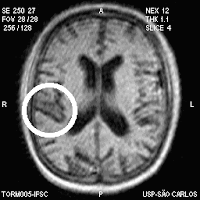

Caso Clínico (Tratamento)